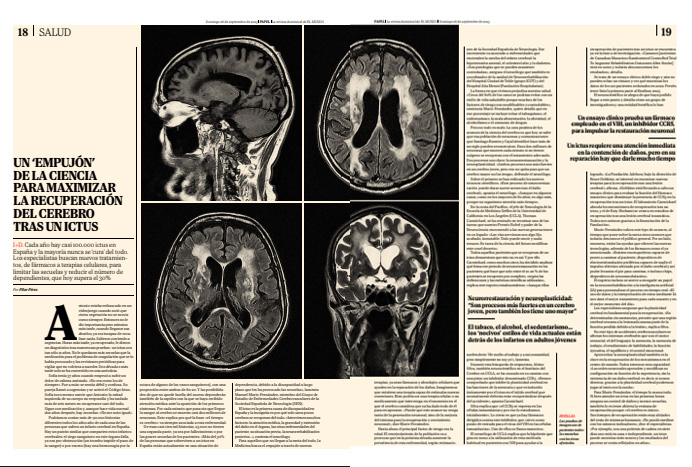

Un “empujón” de la ciencia para maximizar la recuperación del cerebro tras un ictus

Recorte del suplemento Papel de El Mundo

• Ver “Un “empujón” de la ciencia para maximizar la recuperación del cerebro tras un ictus” en Papel | El Mundo